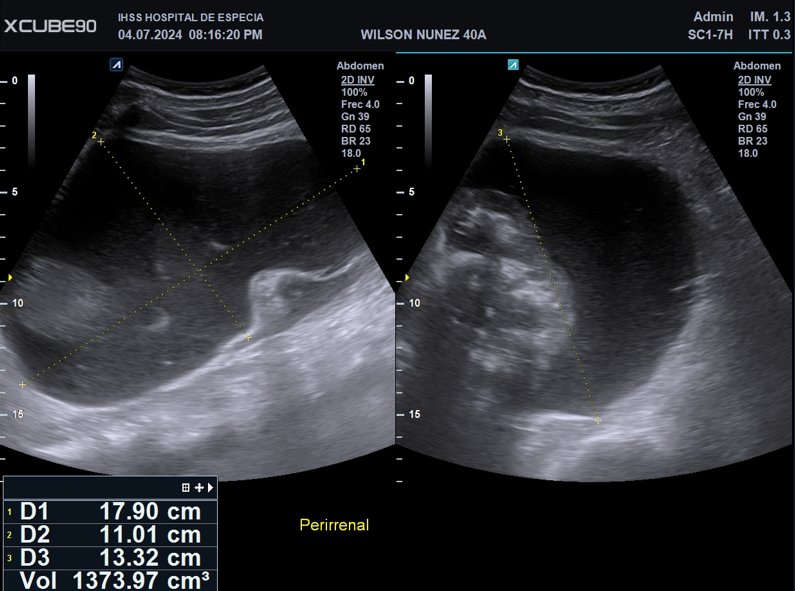

Imagen 2. Imagen de ecografía escala 2D donde se muestra colección perirrenal derecha, con escaso ecos móviles.

Colección perirrenal heterogénea, sin ecos, septos ni tabiques. Aparenta estar contenida dentro de fascia perirrenal con volumen total aproximado de 1400ml.